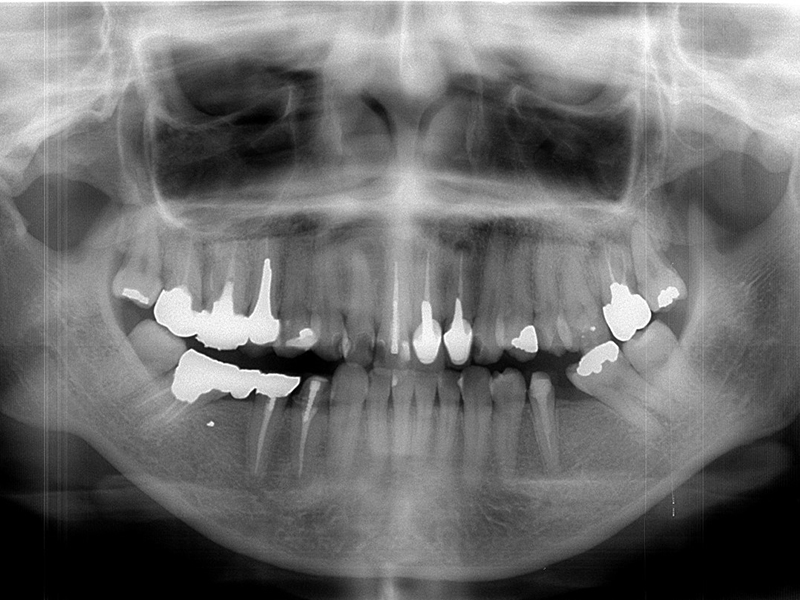

初診時口腔内写真

初診時X線写真

治療終了時

before

after